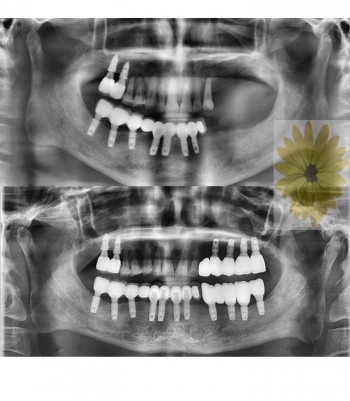

민들레치과 치료 전후사례